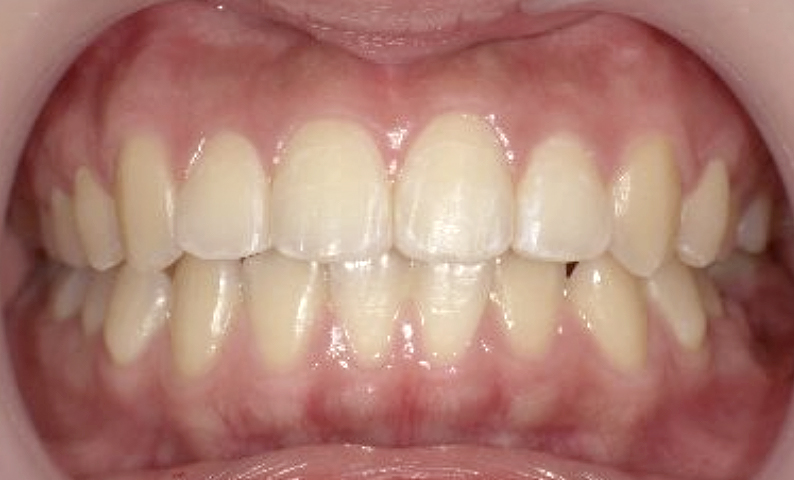

症例_025 上下顎の部分矯正

治療期間:13ヶ月金額:51万円+税女性前歯のガタガタ出っ歯

| Before | After |